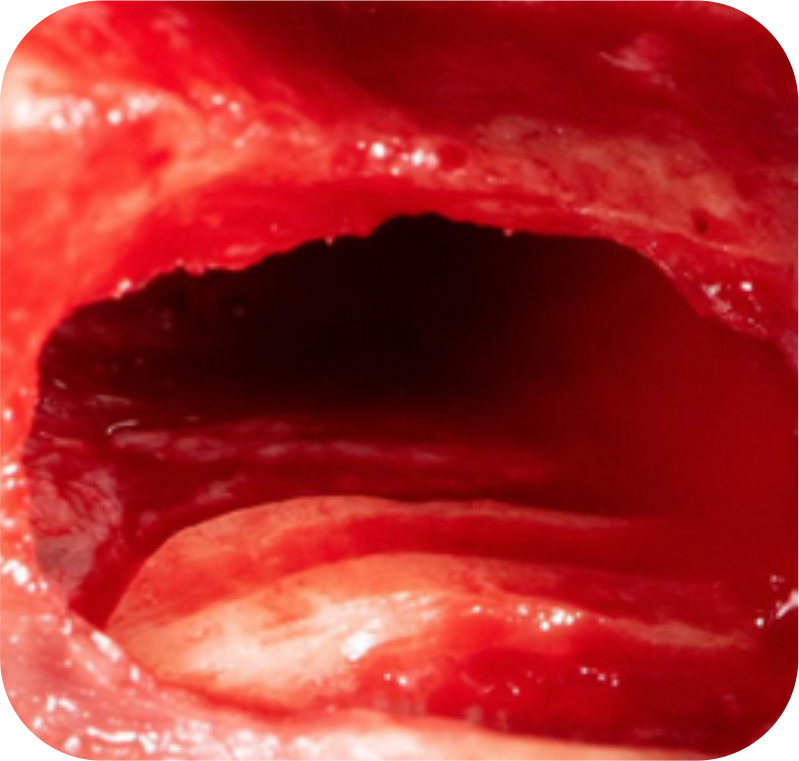

Descolamento da membrana de Schneider, seleção do tipo de enxerto, condições ideais para colocar o implante e locais de incisão são uma dificuldade para você?

Planeje antes de executar! O que parece complicado, você vai fazer de uma forma replicável e descomplicada na Imersão Sinus. Tenha a confiança e conhecimento necessário para planejar com excelência as técnicas de Sinus Lift.

A Imersão traz um dia completo de treinamento sobre as técnicas, biomateriais e sutura, para que você pratique e simule todos os movimentos delicados que envolvem o Levantamento de Seio Maxilar.